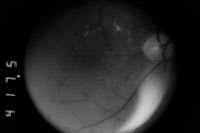

His corrected VA was 20/30 in both eyes. Clinical examination revealed diabetic retinopathy with disc neovascularization in the right eye and 4-quadrant retinal neovascularization and diffuse clinically significant macular edema in both eyes (Figure 2). Following informed consent high-density/low-intensity panretinal and macular SDM was performed for each eye under topical anesthesia in separate sessions.

The patient was lost to follow-up until November 2001 when he returned with corrected VAs of 20/60 right eye and 20/40 left eye. Clinical examination revealed persistent or recurrent diffuse macular edema, some fibrosis of the retinal neovascularization in both eyes, and a preretinal hemorrhage in the left eye. Additional SDM macular photocoagulation was performed December 2001, March 2002, August 2003 (both eyes), and October 2003 (right eye only). Additional panretinal SDM was performed in both eyes December 2001, March 2002, November 2002, and October 2004. During this period of time his macular edema resolved and VA improved. The areas of neovascularization in both eyes demonstrated arrest, arterialization, and fibrosis without contraction, visually significant hemorrhage, or traction retinal detachment. In January 2006 his corrected VA was 20/30 right eye and 20/25 left eye. Intravenous fundus FA revealed persistent leakage from the clinically involutional neovascularization (Figure 2).

Figure 2 A. Preoperative red-free fundus photograph of left eye, January 2001. Note severe background diabetic retinopathy with diffuse clinically significant macular edema. |

Figure 2 B. Preoperative red-free fundus photograph of right eye, January 2001. Note clinically significant macular edema and retinal neovascularization inferior to optic disc. |

Figure 2 C. Preoperative early-phase intravenous fundus fluorescein angiogram, right eye, January 2001. Note early leakage from extensive retinal neovascularization below optic disc. |

Figure 2 D. Preoperative early-phase intravenous fundus fluorescein angiogram of left eye. |

Figure 2 E. Preoperative late-phase intravenous fundus fluorescein angiogram of left eye, January 2001. Note diffuse leakage of dye from both the retina and retinal neovascularization throughout the inferior and temporal aspects of photographic frame. |

Figure 2 F. Postoperative fundus photograph left eye, January 2006. Note resolution of macular edema and fibrosis of pre retinal neovascularization. Note absence of laser-induced chorioretinal scarring. |